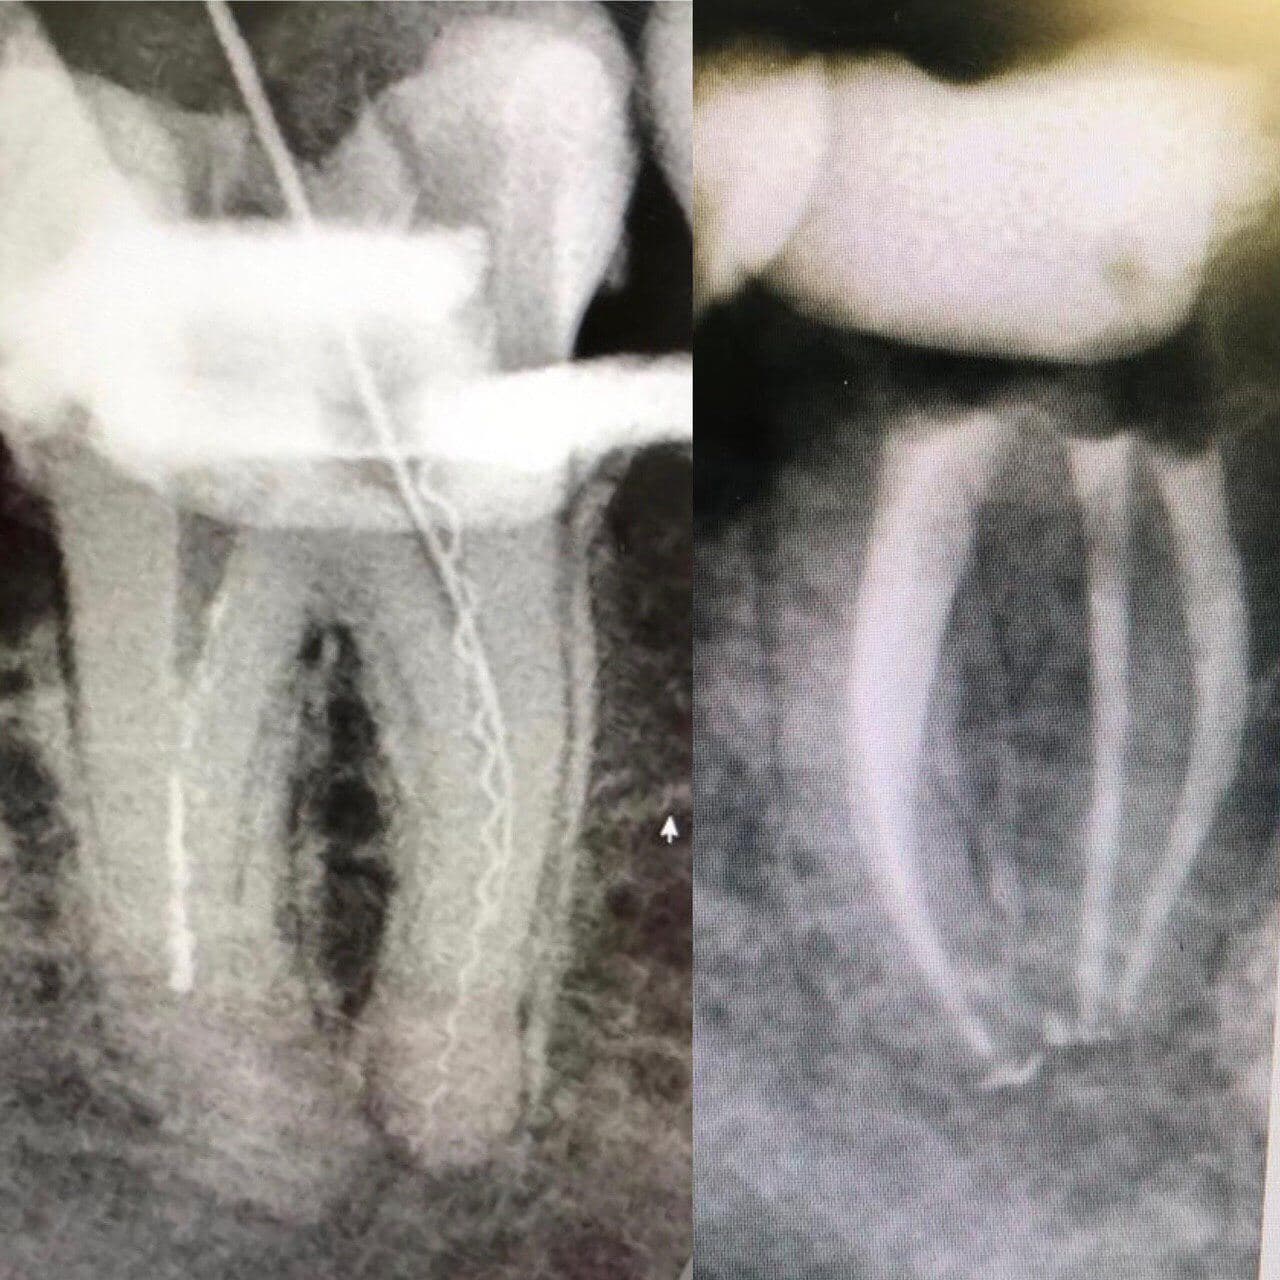

В корневом канале кто-то оставил мне кусок инструмента.